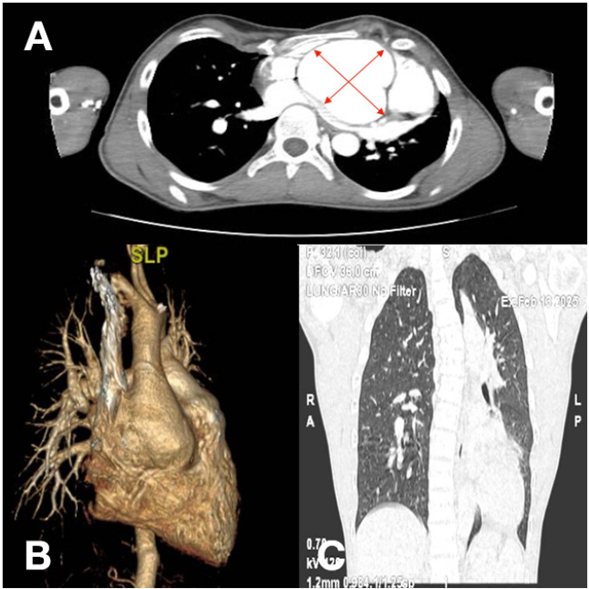

De la valoración preoperatoria, el ETT evidenciaba un ventrículo izquierdo de dimensiones normales con función sistólica global conservada, prolapso valvular mitral con mínima insuficiencia, válvula aórtica trivalva con insuficiencia central de grado moderado y aneurisma de la raíz aórtica de 69 mm. Concomitantemente una angiotomografía de aorta confirmó la presencia del aneurisma de raíz de aorta y porción sinotubular de hasta 67,5 mm, sin compromiso de los restantes segmentos vasculares (Figura 2).

Figura 2 Angiotomografía de aorta. A. Corte tomográfico a nivel de la raíz aórtica que evidencia clara dilatación aneurismática a nivel sinusal con medidas de hasta 67,5 mm (flechas rojas). B. Reconstrucción tomográfica tridimen sional con mayor detalle y resolución espacial. Muestra cómo la dilatación aneurismática se encuentra confinada a la raíz aórtica con preservación de los restantes segmentos distales. C. Corte anteroposterior del cual destacamos la desviación significativa de la columna vertebral a izquierda (parte de los criterios diagnósticos osteoarticulares).